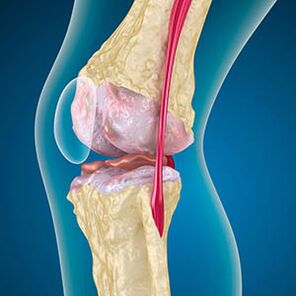

Mat Arthrosis, d'Kieler, déi d'Kante vun de Schanken verléisst ass Abrasioun oder komplett absent. Beschiedegt Tissu ass keng Quell vu Schmerz, well et keng Requestoren huet. Entzündung an den Emgéigend Strukturen verursaacht charakteristesch Symptomer.

De Kierper geet weider d'Erhuelung vu beschiedegt Stoffer, awer den Knorpel gëtt ongläiche. Als Resultat gëtt Onregelméissegkeeten geformt, déi aner Elementer vum Joint verletzen. D'Natur vun der Osteophyte gëtt duerch Kompensatioun fir de glatem Joint Knorpel erkläert. Eng aner Versioun uginn datt de Wuesstum vum "Spurs" Et ass mat engem Versuch verbonnen fir de Joint medial oder lateral ze stabiliséieren wéinst Muskelengewënnung.